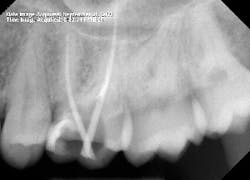

I proceeded to bypass the separated files with a 10 c-file. The apex locator still wasn’t giving me a reading. I was ready to obturate the canal, leaving all the extra metal as fill. Upon drying the canal with paper points, I noticed the paper point disappeared immediately toward the buccal. I took a step back to remove the buccal wall for better access. At this point, I was able to visualize the DB canal much better and was able to remove both of the separated instruments.

After obturation, it became apparent why the apex locator had given no reading for the DB canal. The foramen was located 3–4 mm away from the apex and on a curve that no file could reach. As a result of copious irrigation, the sealer was expressed from the apex.